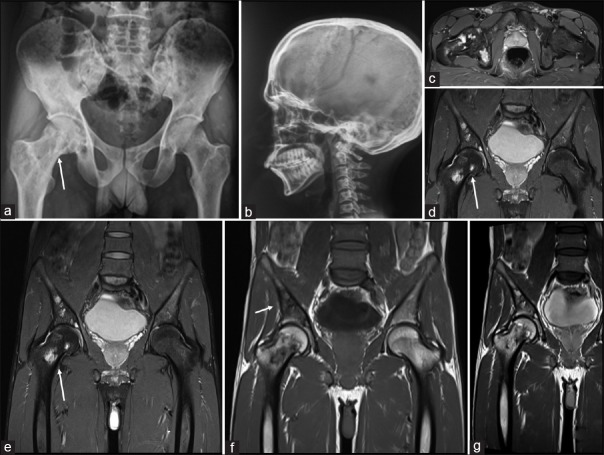

We present a case of a 28-year-old male who presented with headache, back pain, and hip pain of 6 months. There was no history of localized swelling or rise of temperature and no history of weight loss or evening rise of temperature. On examination, there were no focal neurological deficits. Routine laboratory investigations, including total leukocyte counts, differential leukocyte counts, hemoglobin, and platelet counts, were within normal limits. There was a borderline elevation in erythrocyte sedimentation rate. The computed tomography (CT) scan of the cervical spine revealed an ill-defined lytic lesion in the left half of the C3 vertebral body with soft tissue infiltration [Figure 1]. Magnetic resonance imaging (MRI) demonstrated these lesions as iso-hyperintense on T2/fat sat and hypointense on T1-weighted with soft tissue component encasing left exiting nerve root and mildly enhancing heterogeneous adjacent soft tissue component and restricted diffusion [Figures [Figures11 and and2].2]. The MRI and plain radiographs of the calvarium and the spine and pelvis demonstrated multiple lytic lesions in the pelvic bone and absence of calvarial lesions [Figure 2]. However, the skeletal survey did not reveal any other lesions. CT-guided biopsy was performed from C3 vertebral body as it showed features of active lesion. Histopathology showed fibro-collagenous tissue with thin-walled blood vessels infiltrated by eosinophilic micro-abscesses along with sheets of eosinophils that were features are of EG [Figure 3].

| Figure 1:A 28-year-old male presenting with pain (a) axial computed tomography images (bone window) showing an ill-defined lytic lesion in the left half of the C3 vertebral body (black arrow) and (b soft tissue window) soft tissue infiltration (black arrow) confirmed on the (c) gradient T2 axial magnetic resonance imaging, (d) axial T2 magnetic resonance imaging, (e) fat suppressed images axial magnetic resonance images (white arrows) with soft tissue component encasing left exiting nerve root and shows mildly enhancing heterogeneous adjacent soft tissue component and restricted diffusion. (and seen on the sagittal magnetic resonanceimages (I-T2, II-T1, III-fat suppressed, IV-diffusion images) where he C3 body is iso-hyperintense on T2/fat sat and hypointense on T1 weighted